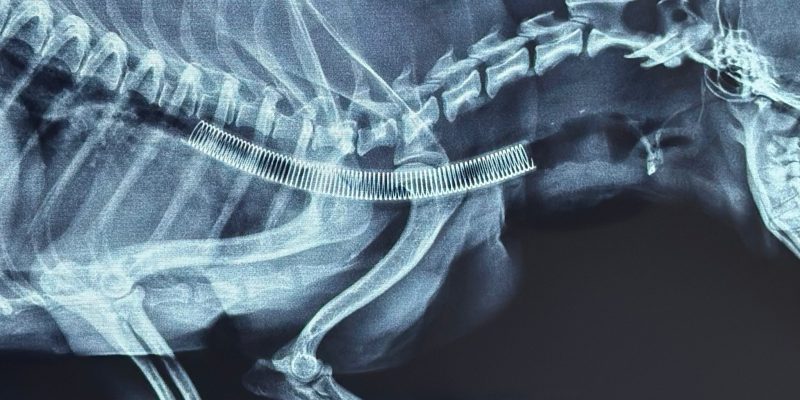

- Giải pháp tối ưu: Đối với các trường hợp hẹp khí quản nặng, việc dùng thuốc chỉ mang tính tạm thời. Đặt Stent khí quản hiện là phương pháp tiên tiến và hiệu quả nhất để giải phóng đường thở, giúp thú cưng hô hấp bình thường trở lại.

Đặt Stent khí quản là một kỹ thuật khó, đòi hỏi độ chính xác cực cao vì:

- Rủi ro cao: Yêu cầu bác sĩ phải có kinh nghiệm dày dặn và tay nghề vững vàng.

- Thao tác chuẩn xác: Các bước can thiệp phải diễn ra nhanh chóng để đảm bảo an toàn cho thú cưng trong quá trình gây mê.